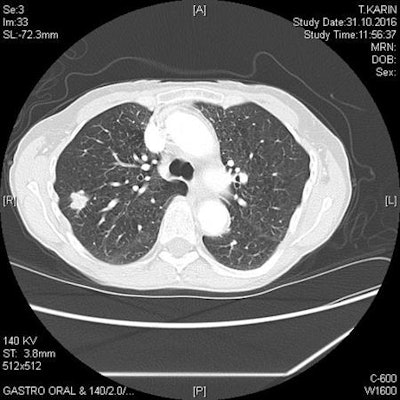

Solid lobulated nodule in the right upper lobe represents non-small cell lung cancer in a 73-year-old female smoker. Image courtesy of Dr. Stefan Diederich, PhD.While the public's wish for a screening program might be there, Diederich said a number of issues were hindering any widespread implementation. For instance, the NLST generated almost more questions than it answered -- for instance, will risk profiles different to those in the NLST benefit from screening, and how long and frequent should the screening regime be?